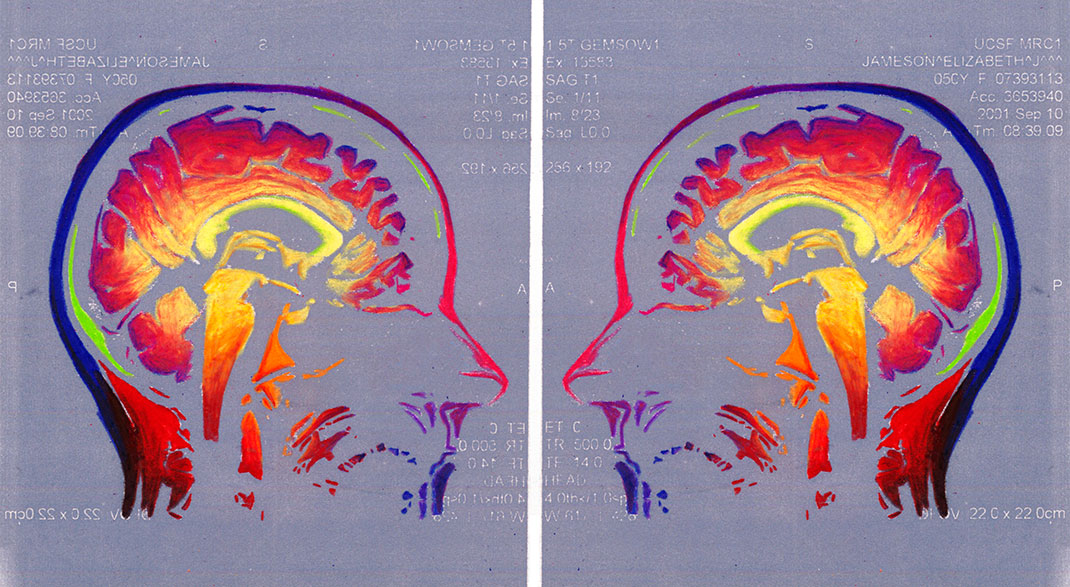

En 1991, elle découvre qu’elle est atteinte de sclérose en plaques. « J’étais en train de jouer avec mes enfants dans un parc. Je n’ai pas eu mal, je n’ai eu aucun signe de quoi que ce soit, j’ai juste découvert que je ne pouvais plus parler. La semaine suivante, les chirurgiens m’ont enlevé une partie du cerveau pour découvrir la source de mon aphasie. Le diagnostic était clair, j’étais atteinte de sclérose en plaques. A partir de ce moment-là, j’ai passé de nombreuses heures dans l’appareil IRM », explique-t-elle.

Elle trouve alors sa source d’inspiration dans sa maladie à travers ses IRMs. « Mes nombreux traitements m’ont donné envie de réinterpréter l’imagerie médicale. Les patients, souvent anxieux, ne voient que laideur et effroi dans les pixels noirs et gris des IRMs. J’ai alors ressenti le besoin vital de les utiliser pour montrer les merveilles et la beauté de nos cerveaux, y compris ceux souffrant d’une maladie. Je veux guérir les patients de la peur de regarder leurs IRMs », s’émeut Elizabeth.

En réutilisant ses scanners, Elizabeth Jameson cherche à insuffler des émotions et des sentiments dans la froideur technologique. Pour cela, elle utilise de nombreux supports : la peinture sur soie ou encore des impressions à partir de gravures sur cuivre ou sur plaque solaire. Ensuite, elle renforce la couleur de ses images grâce à de la peinture, des crayons ou du pastel sec. Le résultat offre une collection brillante, colorée, pleine d’émotion et de symbole.

Maintenant tétraplégique, Elizabeth crée avec l’aide d’un assistant. Selon elle, ses impressions ne sont pas qu’un moyen de faire la chronique des changements de son cerveau, qu’elle qualifie d’« organe le plus sacré ». Son travail est également un moyen de devenir plus familière avec ces changements, pour les rendre moins terrifiants. « Mon art est composé à 90 % de mon cerveau, tout simplement parce que je suis mon cerveau », conclut-elle.